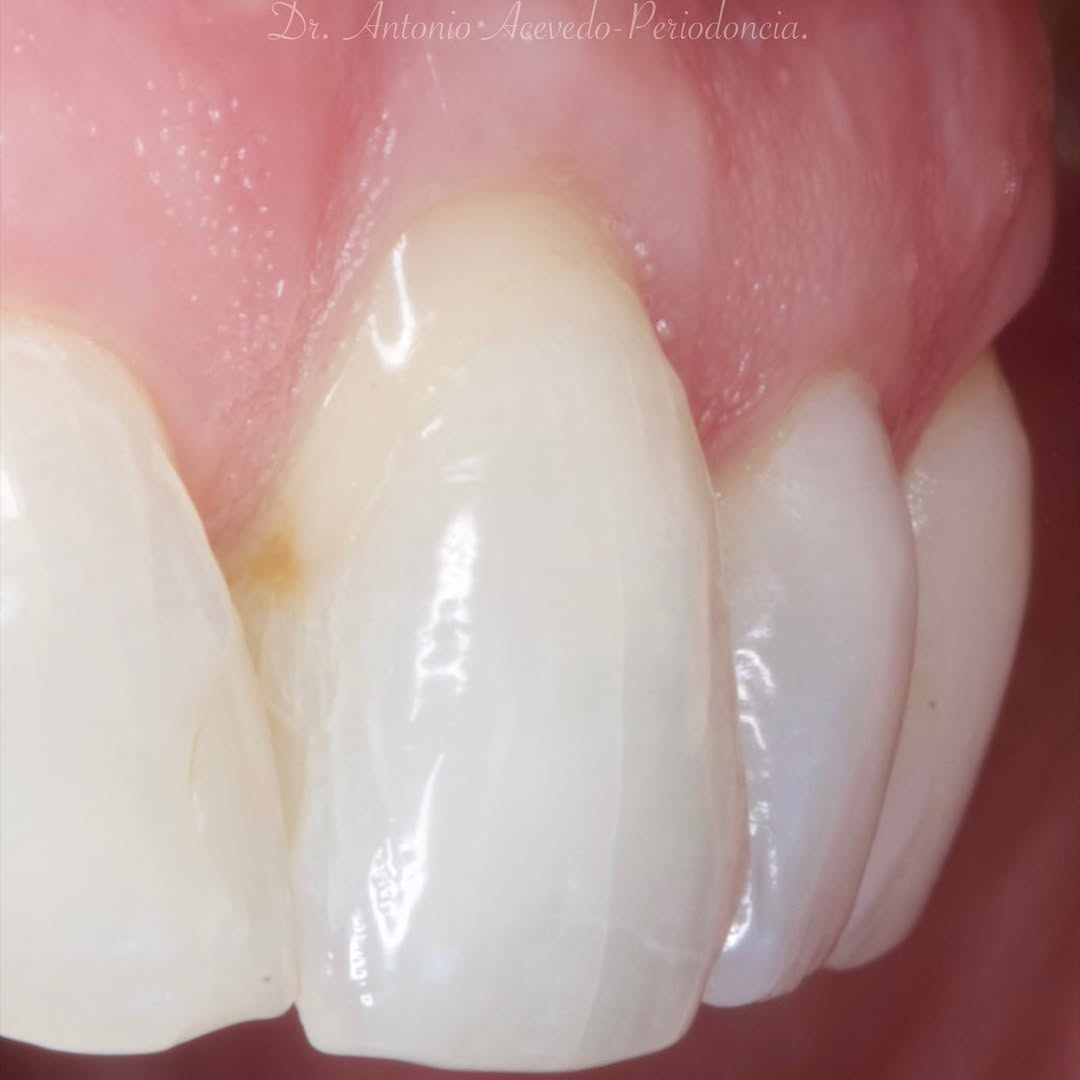

Se presenta un caso clínico de restauración directa en resina composite, ejemplo del valor de la precisión y la técnica meticulosa incluso en procedimientos considerados rutinarios dentro de la práctica diaria. El caso pone en evidencia la importancia del control de la morfología, la textura y la integración cromática, así como del adecuado aislamiento del campo operatorio y la estratificación del material, factores determinantes para conseguir un resultado natural, funcional y duradero. A través de una ejecución cuidadosa, se logró una restauración estéticamente imperceptible y funcionalmente estable, que respeta los principios de mínima invasión y adhesión efectiva. Este tipo de procedimientos, aunque cotidianos, reflejan la constancia y el nivel de exigencia clínica necesarios para ofrecer odontología de calidad en todos los casos, independientemente de su complejidad.

En el actual mundo de los implantes y las restauraciones CAD CAM, los composites directos ofrecen una alternativa mínimamente invasiva y eficaz, capaz de satisfacer las necesidades de los pacientes y superar sus expectativas.

Conocer el Método Bioclear™ para realizar restauraciones Clase II